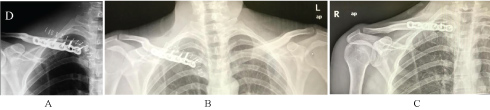

A 33-year-old healthy man was involved in a high-fall during his work, being presented to the nearest emergency department. The initial evaluation was performed according to the ATLS protocol. His complaints were shoulder and neck pain. No open injuries, dyspnea, dysphagia, or numbness were reported, he presented hemodynamically stable. X-rays and CT-scan were performed and revealed a right posterior displaced medial clavicle fracture, close to but with no compression of the underlying neurovascular or gastro or airway structures (See Figures 1). Due to these findings, it was determined that he would require surgery for an open reduction an internal fixation of the right medial clavicle fracture, for which appropriate consent was obtained.

Figure 1: Pre-op 2D and CT- scan 3D reconstruction; Axial and coronal views. View Figure 1